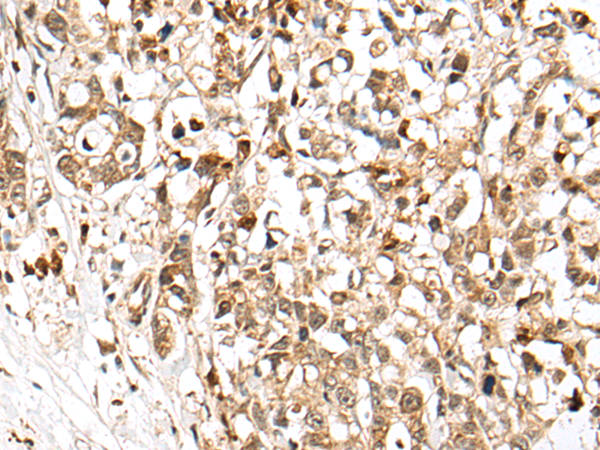

分类: 科研抗体货号: P09403别名: DVC1; PRO4323; spartan; C1orf124应用: IHC反应种属: Human, Mouse, Rat